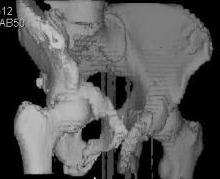

Уважаемые коллеги! Девушка 18л сросшиеся переломы лонных, седалищных костей с обеих сторон, перелом крестца справа,перелом костей голени справа (зио), 3 мес после травмы, АВФ снят с таза.

Патологической подвижности нет. Стоит самостоятельно, ходит с костылями, поскольку 3 месяца практически не ходила. Беспокоит выступание лонной кости в области лобка, хотя объективно грубого косметического дефекта нет. На кт разворот лонной кости в сагиттальную плоскость. Вопрос: стоит ли добиватьсяполной репозиции или же достаточно произвести остеотомию верхушки выступающего отломка?

Предварительный диагноз- посттравматическая вертикальная нестабильная деформация таза II степени, неправильно срастающийся перелом боковой

массы крестца справа, правой лонной и седалищной костей, застарелый разрыв лонного сочленения.

Для уточнения диагноза ниеобходимы обзорные рентгенограммы таза (прямая и inlet), Кт срезы на уровне переломов для определения степени сращения и решения вопроса о методе оперативного восстановления анатомии (делать ли остеотомию, низводить ли задние отделы), ни о какой "остеотомии выступающих отломков" тем более у девочки 18 лет речи быть не может.

Предоставляю срезы. Если пациентку функционально ничего не беспокоит, стоит ли навязывать ей лечение.